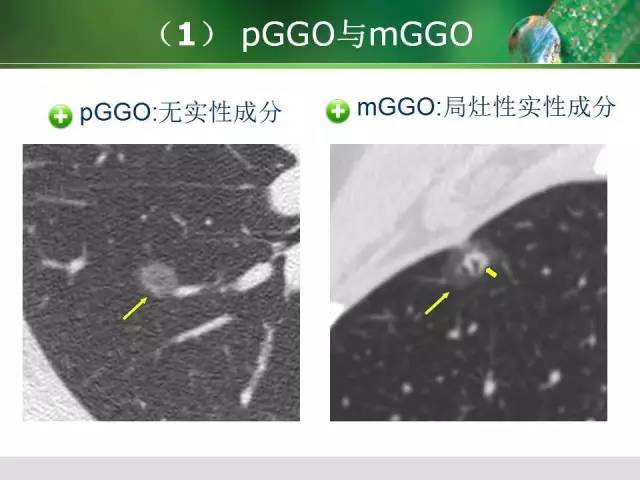

肺部分叶和分段影像解剖  肺磨玻璃密度阴影GGO 的CT诊断与处理

肺磨玻璃密度阴影GGO 的CT诊断与处理  “院长要求医生给所有病人开中药”?当地通报:停